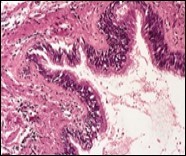

Figure 4.Cutaneous ciliated cyst with a ciliated, pseudostratified columnar epithelium and vascularized fibrous tissue stroma (13).

Typically, cutaneous ciliated cyst is a simple cyst which demonstrates a layering of pseudostratified ciliated columnar epithelium recapitulating conventional epithelial lining of the fallopian tube. As the cutaneous ciliated cyst demonstrates a morphological similarity to the fallopian tube lining epithelium, a Mullerian origin is indicated. Gross examination of cutaneous ciliated cyst depicts a solitary, mobile, non-tender, fluctuant, firm or soft to cystic lump with a fibrous wall and abundant amount of circumscribing adipose tissue. Cutaneous ciliated cysts are of a variable dimension. Cut surface usually displays a unilocular cyst impacted with clear, serous fluid, an attenuated smooth, greyish/ white cyst wall incorporated with incomplete septa traversing the cyst 6, 7.

Cutaneous ciliated cyst is layered with a singular layer of ciliated epithelial cells which are chiefly constituted by cuboidal to columnar epithelium, traversed by partially configured fibrous tissue septa with an admixture of randomly dispersed, intraluminal papillary projections akin to those cogitated in the fallopian tube. Superimposed epithelium is inundated with well vascularized, parallel bundles of collagen although smooth muscle is absent 7, 8.

Cystic structures cogitated within deep dermal or subcutaneous tissue can be impacted with haemorrhagic fluid. Cyst lining is smooth, regular and is essentially composed of a singular layer of columnar epithelium with focally pseudostratified columnar epithelium, a circumscription of loosely configured, well vascularized, fibroconnective or fibrocollagenous tissue and an absence of inflammatory infiltrate.